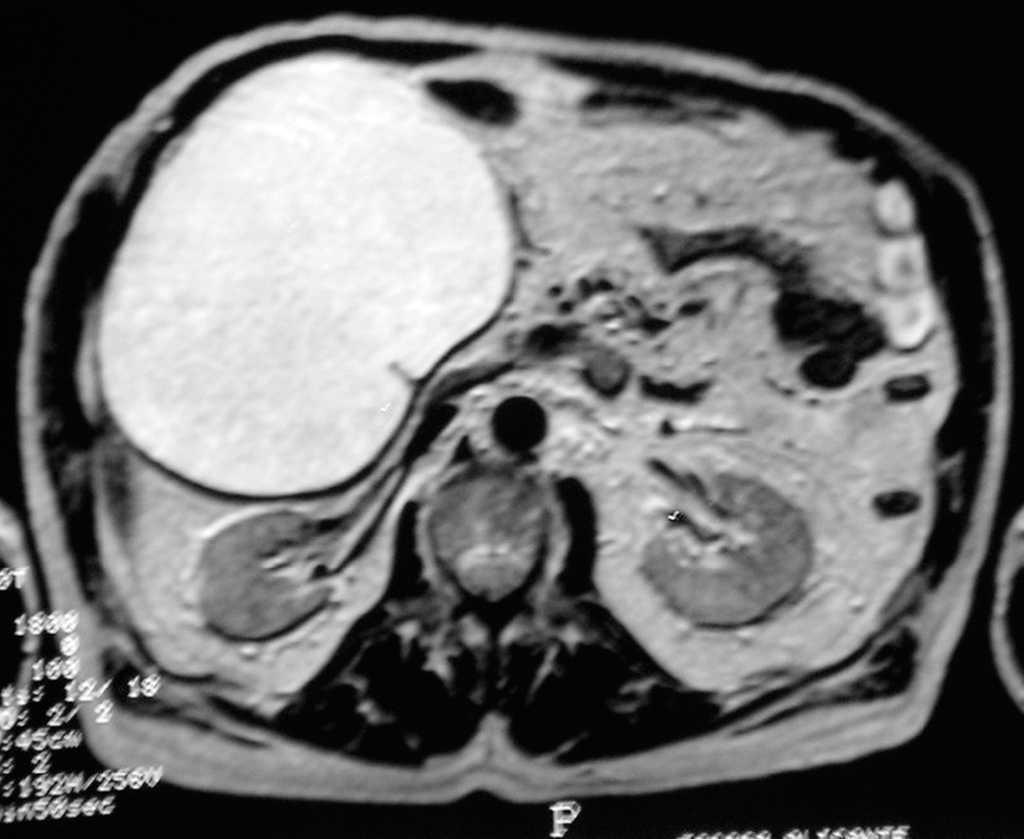

La analítica (hemograma, bioquímica, coagulación) y los marcadores tumorales (antígeno carcinoembrionario [CEA], CA-125 y CA-19,9) fueron normales. La ecografía, la tomografía computarizada (TC) y la resonancia magnética (RM) abdominopelviana (fig. 1) mostraron una gran lesión de aspecto quístico que ocupaba todo el hemiabdomen derecho, bien delimitada, y que no afectaba a estructuras vecinas de probable origen intraperitoneal; como diagnósticos más probables se sugería: quiste hepático, "megavesícula" o tumor suprarrenal. Se completó el estudio con una gastroscopia, una colonoscopia y un tránsito gastrointestinal, que informaron resultados normales.

Fig. 1.